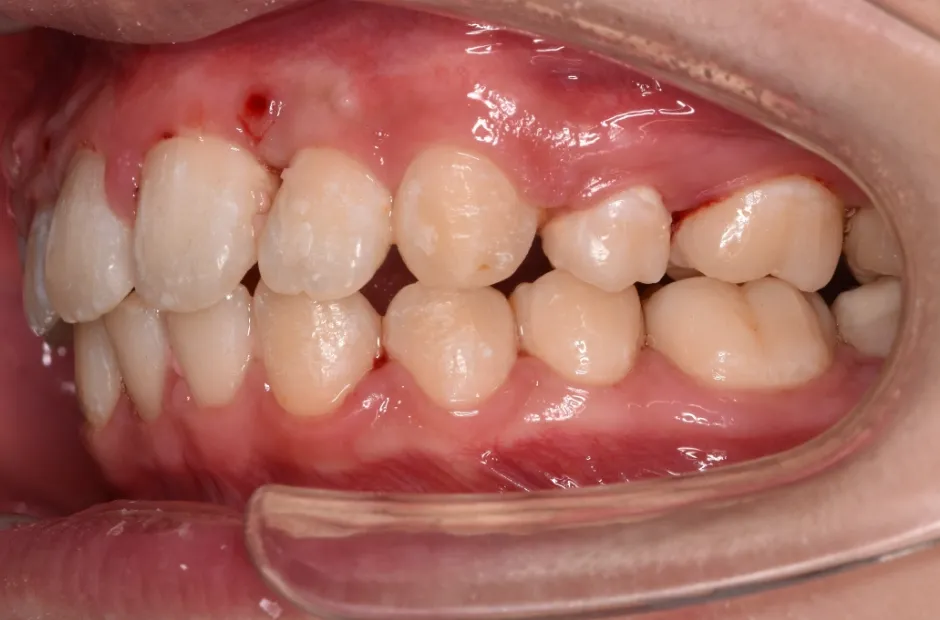

ゆがみ(左右非対称)

| 診断名・主訴 | ゆがみ(左右非対称) |

|---|---|

| 年齢・性別 | 20歳・女性 |

| 治療期間・回数 | 2年半 30回 |

| 治療に用いた主な装置 | 急速拡大 アンカー |

| 抜歯部位 | 左右上5番 |

| 治療費 | 70万円(税抜) |

| リスク・副作用 | 装置による違和感・疼痛・歯肉退縮・歯根吸収・虫歯のリスクなど |

治療前